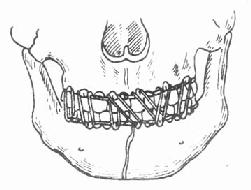

2.牵引复位:颌骨骨折后,经过较长时间(上颌骨三周以上,下颌骨四周以上),骨折处已有部分纤维组织愈合,手法复位不成功,可采用牵引复位法。下颌骨骨折多用颌间牵引,就是在下颌骨有移位的骨折段上安置分段牙弓夹板(图4-16),然后在与上颌的牙弓夹板之间,用小橡皮圈作弹性牵引,使之逐渐恢复正常的咬合关系。上颌骨骨折后,如骨折段向后移位,可在上颌牙列上安置牙弓夹板,在头部制作带有金属支架的石膏帽,在牙弓夹板与金属支架之间作弹性牵引,使上颌骨骨折段向前复位(图 4-17)。需要较大牵引力时,也可作卧式重力性牵引。

分段式牙弓夹板

图4-16 分段式牙弓夹板图4-17 金属支架石膏帽,将上颌骨骨折段向前牵引复